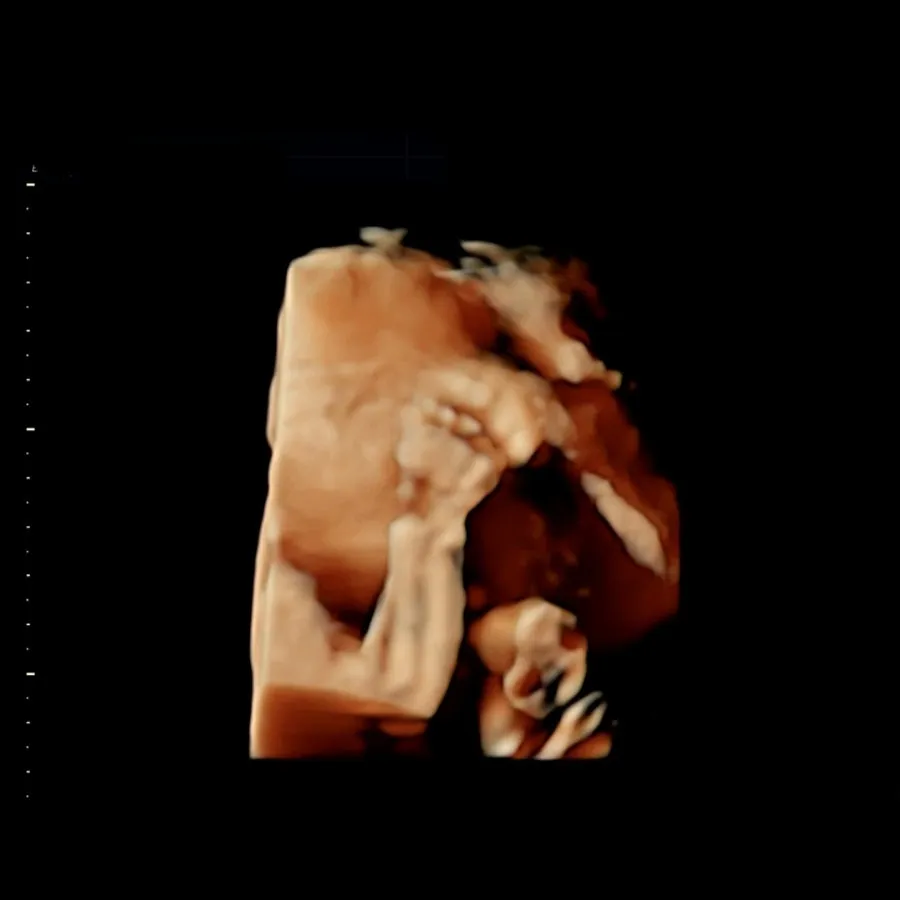

이번 주는 얼굴을 아예 가리고 있어 입체 초음파를 보지 못했지만, 다행히 지난 진료의 입체 초음파에 선명하게 얼굴을 보여준 사진이 있어 괜찮았다. 비록 얼굴 앞의 손을 내려주진 않았지만 실시간으로 입체 초음파를 보며 수시로 손을 쥐었다 펴며 꼼지락거리는 아기가 너무 귀여웠다.